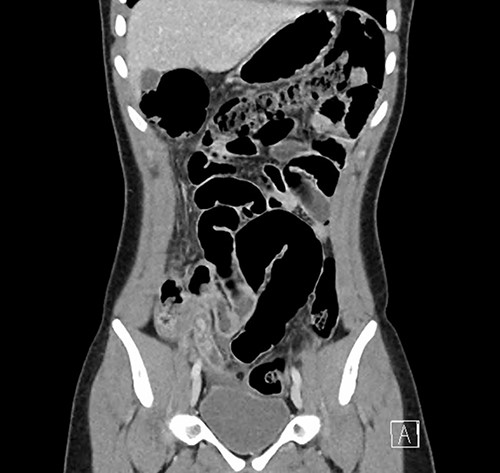

Investigations were arranged. His white cell count was 15.5 x 109/L and C reactive protein was 117 mg/L. An ultrasound of the abdomen showed a small volume of free fluid in the right iliac fossa but did not identify the appendix. A computed tomography (CT) scan of the abdomen was performed, which showed that the appendix was dilated to 13 mm with associated peri-appendiceal fat stranding and several hyperdensities measuring up to 8 mm within the base of the appendix (Figs 1 and 2).

Coronal CT image demonstrating the inflamed appendix containing hyperdensities.